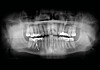

I dommen som falt to år og fire måneder senere, står det at eleven slår ham flere ganger i ansiktet med knyttet hånd, samt slår og/eller sparker ham mot kroppen og beina. Lien blir påført neseblod, bloduttredelse under høyre øye, smerter i ribbeina og i venstre hofte/lår. I tillegg sprakk to av tennene.

Han kom seg til legen. Der ble han sykemeldt. En undersøkelse hos tannlegen viste at to av tennene hadde sprukket.

– Tannlegen sa det var umulig å få slike skader av å tygge, det måtte komme fra slag. Han sendte bekreftelse til Nav, og ganske snart ble dette registrert som en yrkesskade.